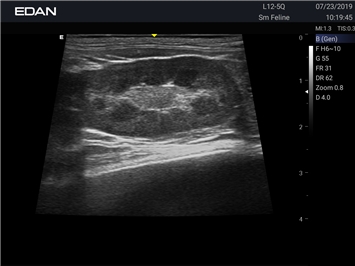

EDAN Acclarix AX2 VET

Ветеринарный ультразвук одним нажатием. Система Acclarix AX2 VET разработана с целью обеспечить бескомпромиссную производительность по доступной цене. Наличие уникальных двойных аккумуляторов в легком корпусе массой 4,5 кг из магниевого сплава позволяет системе Acclarix AX2 VET удовлетворять все потребности ветеринарных исследований, сохранив низкую стоимость.

EDAN Acclarix AX2 VET представляет собой специализированную ветеринарную ультразвуковую систему, сочетающую высокую производительность с доступной ценой. Благодаря продуманной конструкции и передовым технологиям, система обеспечивает качественную диагностику животных различных видов.

• Высокое разрешение для детальной диагностики

• Улучшенная визуализация глубоко расположенных органов